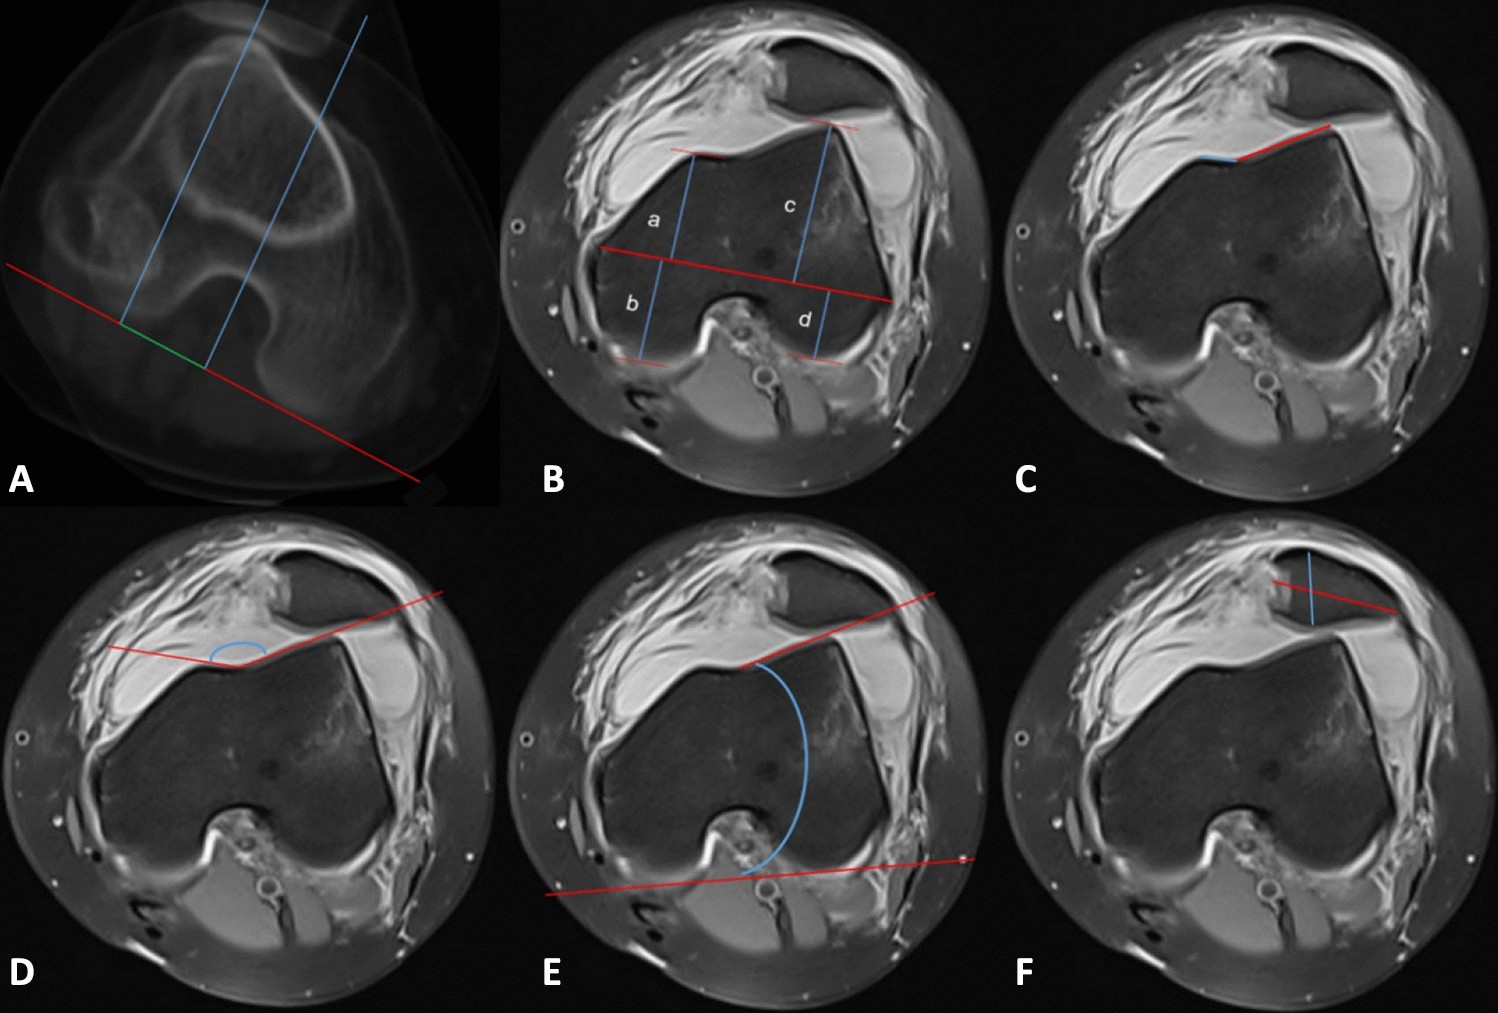

Figure 2

Morphological measurements of the trochlear and patellar regions were conducted as follows: (A) TT-TG measurement; (B) condylar length measurement in the following regions: (a) anteromedial condyle, (b) posteromedial condyle, (c) anterolateral condyle, (d) posterolateral condyle; (C) Measurement of medial and lateral trochlear facet lengths; (D) sulcus angle measurement; (E) LTI measurement; (F) patellar width and thickness measurement.